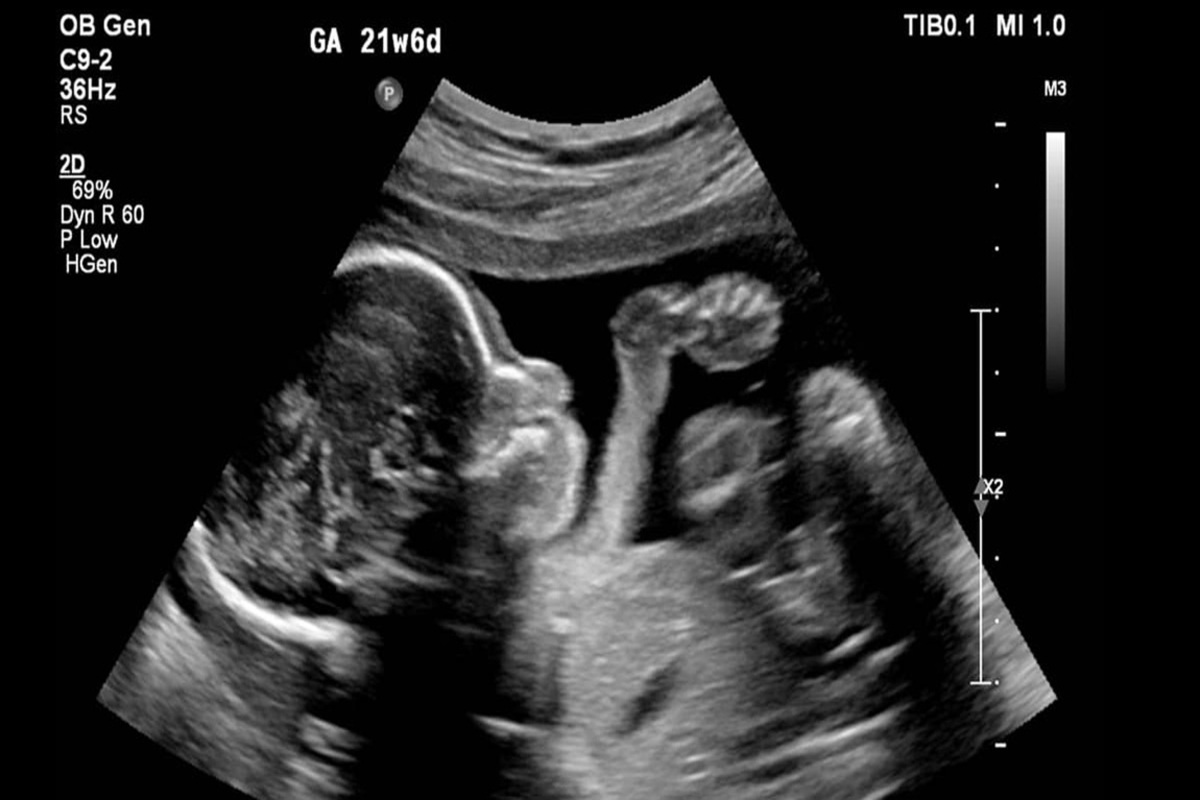

رویداد۲۴ یاسر مختاری: سقط جنین پزشکی یا کورتاژ نوعی سقط جنین عمدی است که با مجوز قانونی تا پیش از هفته هجدهم بارداری از سوی پزشک معالج صورت میگیرد. این نوع سقط جنین برای پایان دادن به باداریهای خطرناک استفاده میشود که عموما با توصیه پزشک و با صدور مجوز از سوی پزشکی قانونی همراه است.

به سقط جنین پزشکی، سقط درمانی نیز گفته میشود که علاوه بر پایان دادن به بارداریهای خطرناک در زمانی پس از آزمایشهای گوناگون مشخص شود که جنین غیر طبیعی است نیز تا پیش از هفته دوازدهم بارداری مورد استفاده قرار میگیرد. در بیشتر کشورهای جهان زمانی از سقط درمانی استفاده میشود که نخست برای نجات جان مادر باردار و حفظ سلامت او و پایان بخشیدن به باداریهایی است که همراه با اختلالهای مادرزادی جنین است که در تضاد با حیات نوزاد بوده و پس تولد موجب بیماری شدید و غیر قابل علاج نوزاد میشود.

این روش عموما برای اتمام بخشیدن به بارداریهایی انجام میشود که در زمان هفته چهاردهم تا بیست و یکم قرار دارد. این روش با استاع و کورتاژ شباهت دارد اما با ابزارهای بزرگتر دهانه رحم را باز شده و مکش همراه با فورسپس یا سایر ابزارهای دیگر تمام بافتهای جنین را بر میدارد. زمان این جراحی نسبت به دیگر عملها بیشتر طول میکشد.